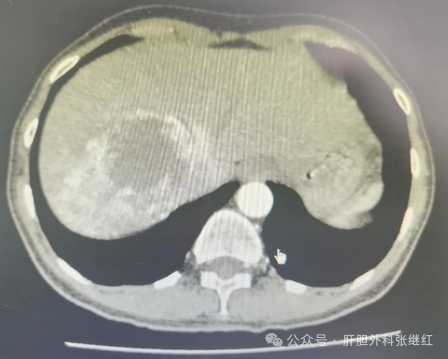

浅谈腹腔镜肝血管瘤切除术

肝血管瘤是先天发育异常或后天内分泌障碍所致的肝脏良性疾病。大多数肝血管瘤体积小、生长缓慢、对机体无不良影响,不需要治疗,更不需要手术治疗。临床上肝血管瘤的手术适应证非常有限。由于肝血管瘤系良性病变,不发生癌变和转移,即使需要手术只需达到去除瘤体的目的即可,一般不需要规则性肝叶、肝段或半肝切除,这样可最大限度地保留正常肝组织。因此,目前主流观点认为,治疗肝血管瘤的最佳手术方法是肝血管瘤切除或剥除术。在微创技术引领外科手术发展方向的今天,具有微创优势的腹腔镜肝血管瘤切除术逐渐得到广大医生和患者青睐。

张继红医生团队对最难显露的肝右后叶上段(S7段)血管瘤进行腹腔镜手术切除时发现:由于血管瘤边界清晰,周围是正常肝组织,切除时解剖清晰,且不需要解剖性肝段切除,手术难度显著低于S7段肝癌切除。因此,张继红医生提示,对确诊且需要手术治疗的肝血管瘤患者,建议优先选择腹腔镜肝血管瘤切除(剥除)术。当然,任何时候不能违背“手术安全第一,微创技术第二”的原则。